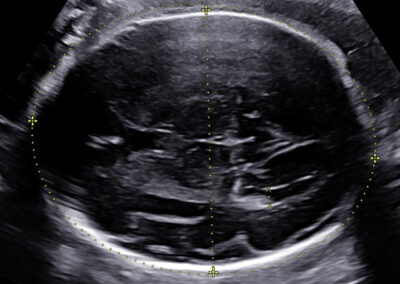

Používáme špičkové přístroje a všichni naši lékaři jsou držiteli certifikátu Fetal Medicine Foundation (FMF) na všechny typy ultrazvukových vyšetření v těhotenství. Při vyšetření miminka se vždy řídíme FMF protokoly, prohlížíme i drobné detaily a ke zpřesnění používáme kombinaci 2D a 3D ultrazvuku. V průběhu vyšetření vám vždy vysvětlujeme, co právě vyšetřujeme a co s námi můžete vidět na monitoru. Po skončení vyšetření vám srozumitelně vysvětlíme výsledky (a případně závažnost situace) a navrhneme další postup.

Každé z vás věnujeme dostatek času, přistupujeme k vám individuálně a respektujeme vaše rozhodnutí ohledně volby dalšího postupu. Přítomnost partnera či někoho blízkého je u nás samozřejmostí. Po vyšetření od nás vždy obdržíte podrobnou zprávu elektronicky, u většiny vyšetření i fotografie miminka a případně DVD záznam na námi poskytnuté médium. Ultrazvukového vyšetření se nemusíte obávat, žádným způsobem neohrožuje zdraví a život váš, ani vašeho miminka.